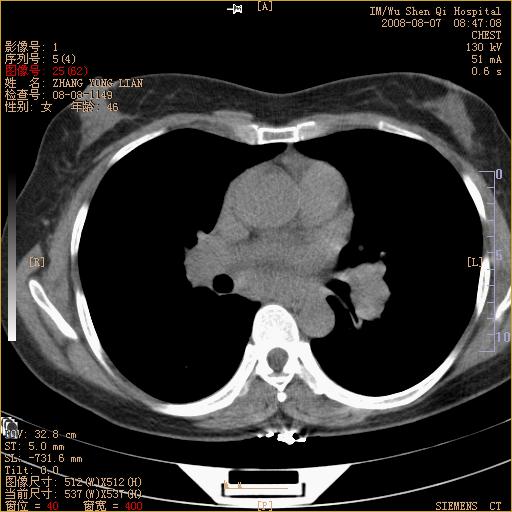

标题: CT15050:女,46岁,咳嗽胸痛一月余 [打印本页]

纵隔窗没发全,左下肺近胸膜处结节。有长毛刺,纵隔淋巴结增大,不排除恶性病变。

考虑肺癌

考虑左肺下叶后基底段周围型肺癌伴纵隔淋巴结转移可能性大。

左下肺ca并纵隔及左肺门区淋巴结转移。

脾脏低密度结节转移不排除。

1)考虑左肺下叶后基底段周围型肺癌伴纵隔淋巴结转移。2)脾内低密度灶,性质待定;不排除转移瘤可能。